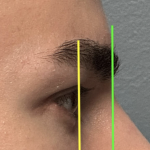

People considering custom jawline implants tend to ask a consistent set of questions. These generally fall into four categories: outcomes, safety, process, and recovery. What are custom jawline implants? Custom jawline implants are patient-specific implants designed from a 3D CT scan of your face. Unlike standard implants, they are digitally created to match your exact Read More…